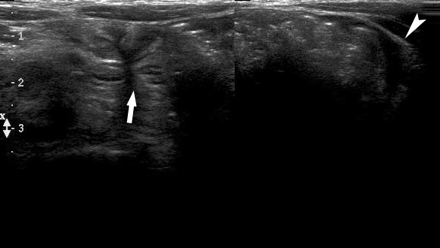

6岁大的女孩出现腹痛并呕吐,脐部左上有一不清晰的肿块,此次发作的大约10天前曾有过持续约数小时的类似症状,临床考虑肠套叠。超声显示脐部左侧有2处扩张的肠管,临界区位于中线处,这2处肠管有薄的包膜覆盖—之所以能看到包膜是因为囊内和腹腔存在少量积液(图7)。病人没有做进一步的检查,根据其临床病情进行了腹腔镜检查,发现十二指肠左侧的腹内疝,在疝囊内存在扩张的肠管,这是因为疝囊颈部的输出端肠管梗阻而导致的。

图7:左侧腹部的组合横向扫描显示疝囊内的扩张肠管(短箭头),疝囊周边的液体表明了其轮廓,过渡区位于疝囊的颈部(箭头)。